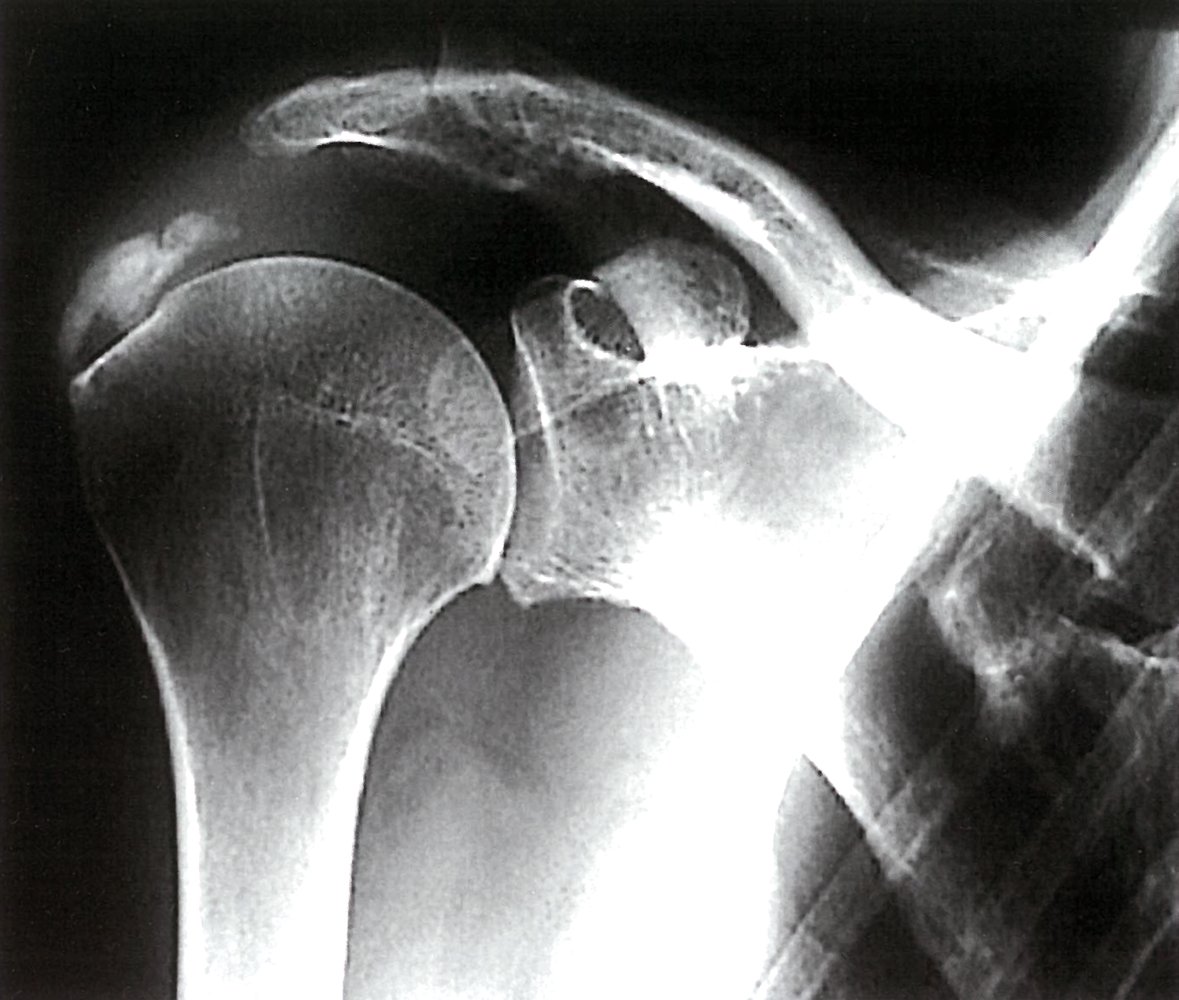

• Imaging

• X-ray shoulder: may show signs of rotator cuff damage

• MRI shoulder: may show large joint effusion, significant rotator cuff tears, synovial hypertrophy, and calcification and destruction of cartilage at the articular surface

Milwaukee shoulder syndrome is associated with an extensive loss of articular cartilage, destruction of the humeral head, rotator cuff defects, large effusion, and small osteophytes. Conversely, OA is typically associated with prominent osteophytes, an intact rotator cuff, and humeral head sclerosis. [9]